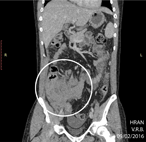

Cecal ameboma mimicking obstructing colonic carcinoma

Mutlaq Almalki and Waed Yaseen

Journal of Surgical Case Reports, Volume 2018, Issue 6, June 2018, rjy124, https://doi.org/10.1093/jscr/rjy124